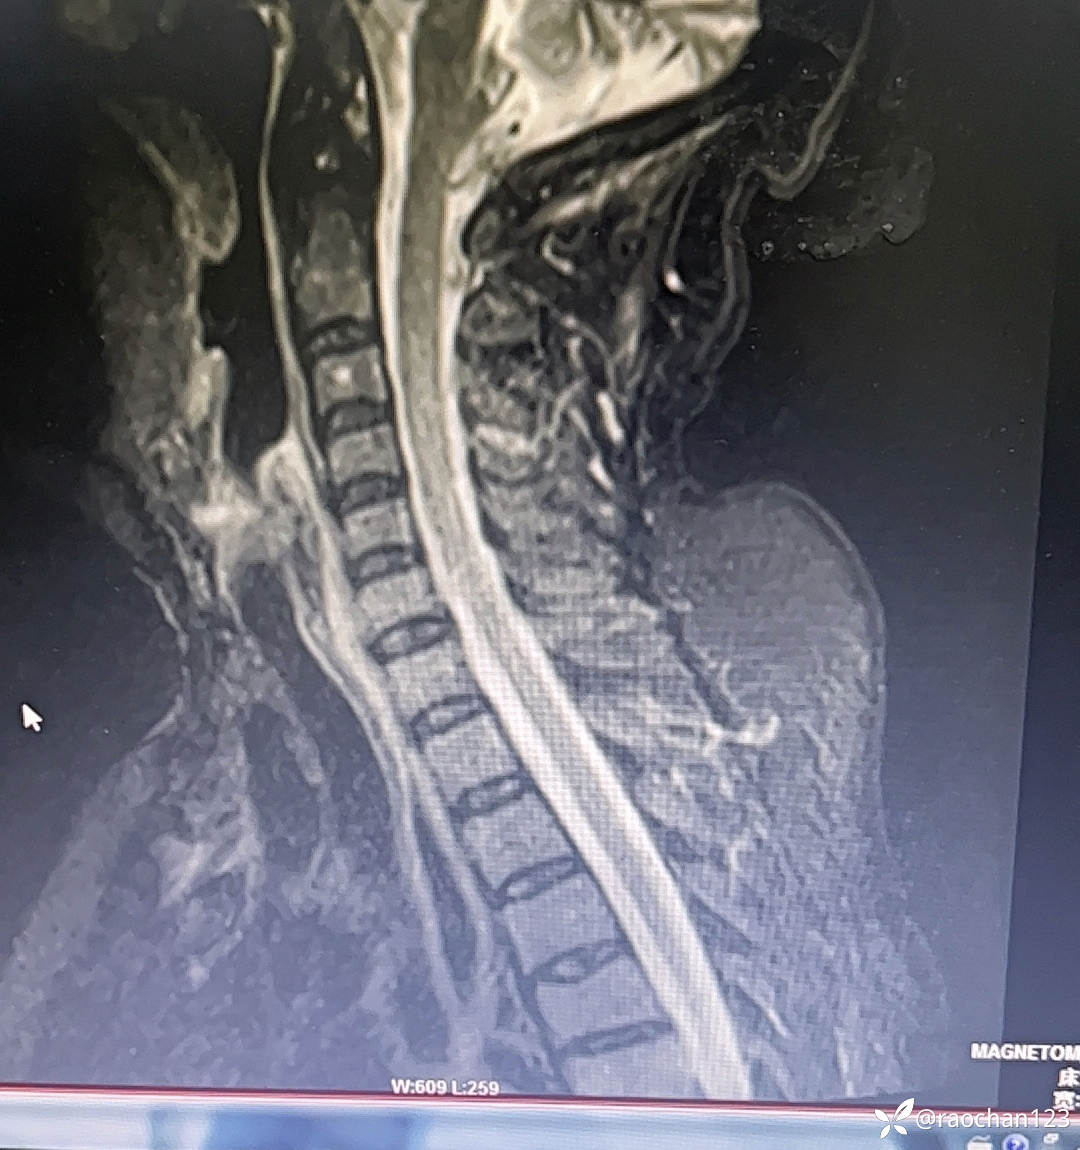

【治疗经过及结果】:给予低流量吸氧,布洛芬混悬液 解热 镇痛,左氧佛沙星抗炎(既往有头孢过敏史)、止痛,热毒宁注射液 清热解毒;艾箱灸、中药塌渍、中药涂擦、火罐、TDP、中药热奄包等中医外治通络祛痛等治疗后,仍有发热,肌酸、肌痛、关节疼痛症状。复查血常规:2024-11-8 13.93# 谷丙转氨酶 45U/L 天门冬氨酸 25U/L 白蛋白 27.0g/L 进一步查乳酸脱氢酶 284U/L 肌酸激酶 26U/L,PCT 0.44ng/ml BNP 811ng/L 免疫五项中IgGA 5.38g/L 血钙 1.94mmol/L 尿微量白蛋白 32.2mg/L 25羟基维生素D 22.68ng/ml 甲胎蛋白、癌胚抗原(-)。颈椎MRI:1.颈椎骨质增生,C4/5、C5/6、C6*7椎间盘轻度突出2、颈后皮下软组织内脂肪堆积,请结合临床。(后颈部皮下软组织内可见异常信号影,T1T2呈高信号,压脂序列呈低信号,颈椎生理曲度变直,椎体后缘连线尚连续,椎体缘骨质光滑,各椎间隙未见狭窄,椎体信号欠均匀,部分椎间盘T2信号减低,C4/5、C5/6、C6/7椎间盘向后轻度突出,硬膜囊轻度受压,椎管无狭窄,黄韧带无肥厚,颈隋未见明显异常)。骨密度:骨质疏松(T值 -4.2)。抗ANA抗体 RF 抗CCP抗体 ENA抗体谱结果待回。患者服用布洛芬混悬液后出现大汗淋漓,血钙偏低,调整为停服布洛芬混悬液、给予醋酸泼尼松10mg 2次/日 口服 解热、抗炎、止痛,金钙尔奇 600mg 2次/日,骨化三醇 0.25ug/日 口服 改善骨质量,暂给予肠内蛋白营养(患者饮食无异常),余治疗同前。